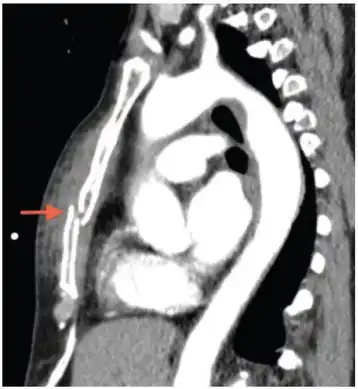

Computed tomography identifying displaced sternal fracture. -